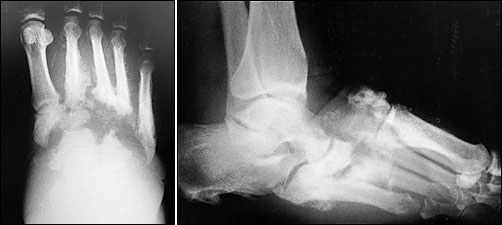

肥厚型通常發生在足部前方,後跟或腳踝,分類上常見有Eichenholtz classification及Brodsky's classification兩種,傳統上及最常用的是根據Eichenholtz classificationsystem來分類15,第一期是發展中,破碎期(acute Charcot),特點是關節旁的骨折及脫臼導致不穩定及變形的腳,如圖2。

圖2 (左及右)影像顯示急性夏兒哥足,並脫臼,導致不穩定的搖椅弧形底的腳rocker-bottom foot

病人在癒合期時coalescence stage (subacute Charcot)表現骨頭碎片的再吸收,在修補,再強化期(chronic Charcot)則表現骨頭碎片的融合,如圖3。

FIGURE 3. Consolidation, or reparative, stage (chronic Charcot).